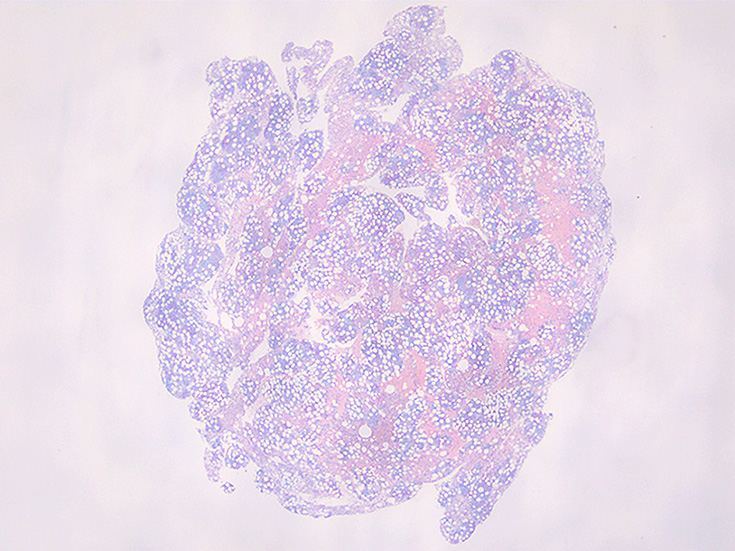

骨髄吸引クロット組織

cellularity 50-60%. 3系統造血細胞の増殖を認める. maturation arrestはない.

特に赤芽球系細胞が強く増殖している所見ではなく, 顆粒球系細胞増多がめだち, 巨核球の増加もある.